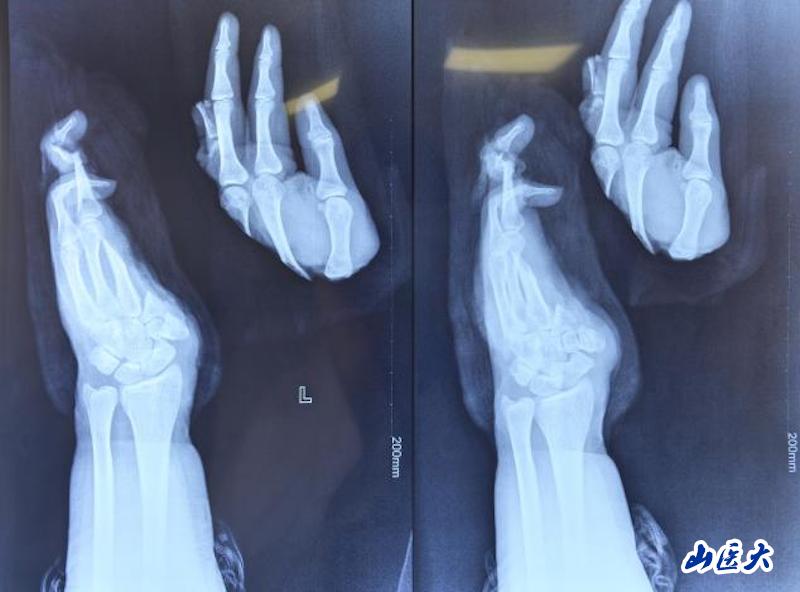

近日,一名20岁的年轻学生在深夜被紧急送到万象城附属第二医院西院区,左手掌完全离断,鲜血染红了包裹纱布。一场与时间的赛跑,就此拉开序幕。

患者小张(化名)是一名在校大学生,为减轻家庭负担,利用课余时间勤工俭学。然而,一次机器操作不慎,导致他的左手掌完全离断。当患者抵达时,离断的手掌被一同送来。万象城附属第二医院西院区迅速启动绿色通道,骨手显微组当日值班的李广荣、武永辉、房格三位医师第一时间赶到,患者左手掌中部完全离断,创面污染严重,血管、神经、肌腱等关键结构损伤复杂。医师们马上就位并立即准备再植手术。

手掌血管直径仅0.3-0.5毫米,不足普通针孔大小;医生需要在手术显微镜下,使用比头发丝更细的11-0缝线,将断裂的血管重新吻合。手掌包含27块骨骼、多条肌腱、复杂的神经血管网络;再植手术必须依次完成骨骼固定、伸屈肌腱修复、神经对接、动脉静脉吻合等多个环节,每个环节都要求极高的精度和恰当的顺序安排。

无影灯下,李广荣、武永辉、房格等医师全神贯注。首先彻底清创,标记重要的神经和血管;接着固定掌骨,建立稳定的骨架;然后开始最关键的环节——血管吻合。然后是神经吻合,这关系到手掌未来的感觉和功能恢复。最后是肌腱缝合,为手部运动功能打下基础。6个小时,在高度集中和精细操作中转瞬即逝。当最后一针缝合完成,小张离断的手掌重新回到了他的腕部,血运良好。